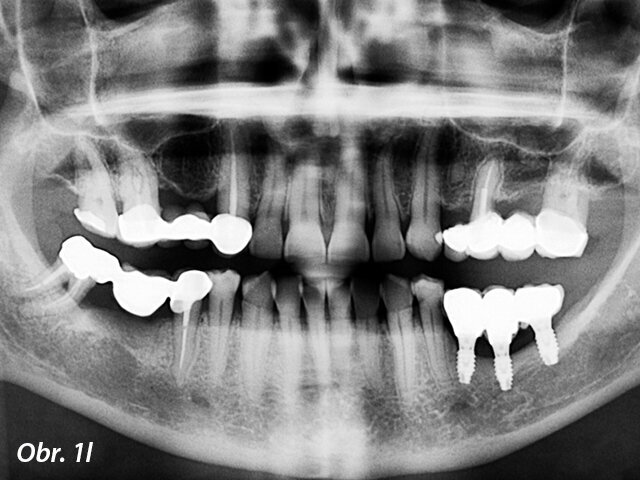

Pacient s dehiscencí ošetřený pomocí GBR s nezanořeným postupem: a) Předoperační panoramatický rentgenový snímek, b) Předoperační pohled na okluzi, c) Atrofie kosti alveolárního hřebene vizualizovaná po odklopení laloku, d) Zavedení implantátů do oblasti 35, 36 a 37, e) Syntetická kost překrývající dehiscenci, f) Resorbovatelná membrána aplikovaná přes kostní náhradu, g) Sutury, h) Zhojené měkké tkáně, i) Okluzální pohled na umístěnou protetickou práci, j) Laterální pohled na protetickou práci

Panoramatický rentgenový snímek tři roky po zatížení